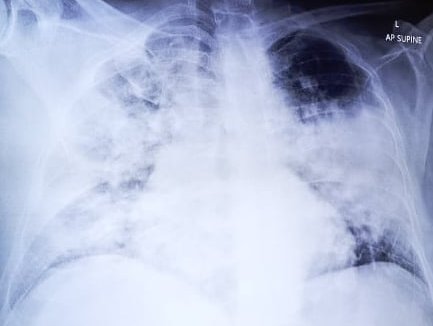

Δημοσιεύοντας την ακτινογραφία ενός ασθενούς με COVID-pneumonia, που δυστυχώς κατέληξε στη ΜΕΘ του Γ.Ν. Λευκωσίας, ο πνευμονολόγος Δρ Αλέξης Παπαδόπουλος παραθέτει τους δύο λόγους για τους οποίους έκανε την εν λόγω ανάρτηση.

PS. Μετά από προβληματισμό, αποφάσισα να αναρτήσω την ακτινογραφία του συγκεκριμένου ασθενή με COVID-pneumonia. Είναι απίστευτο το πώς αυτός ο άνθρωπος πάλευε στο σπίτι με αυτές τις εκτεταμένες αλλοιώσεις στους πνεύμονες.